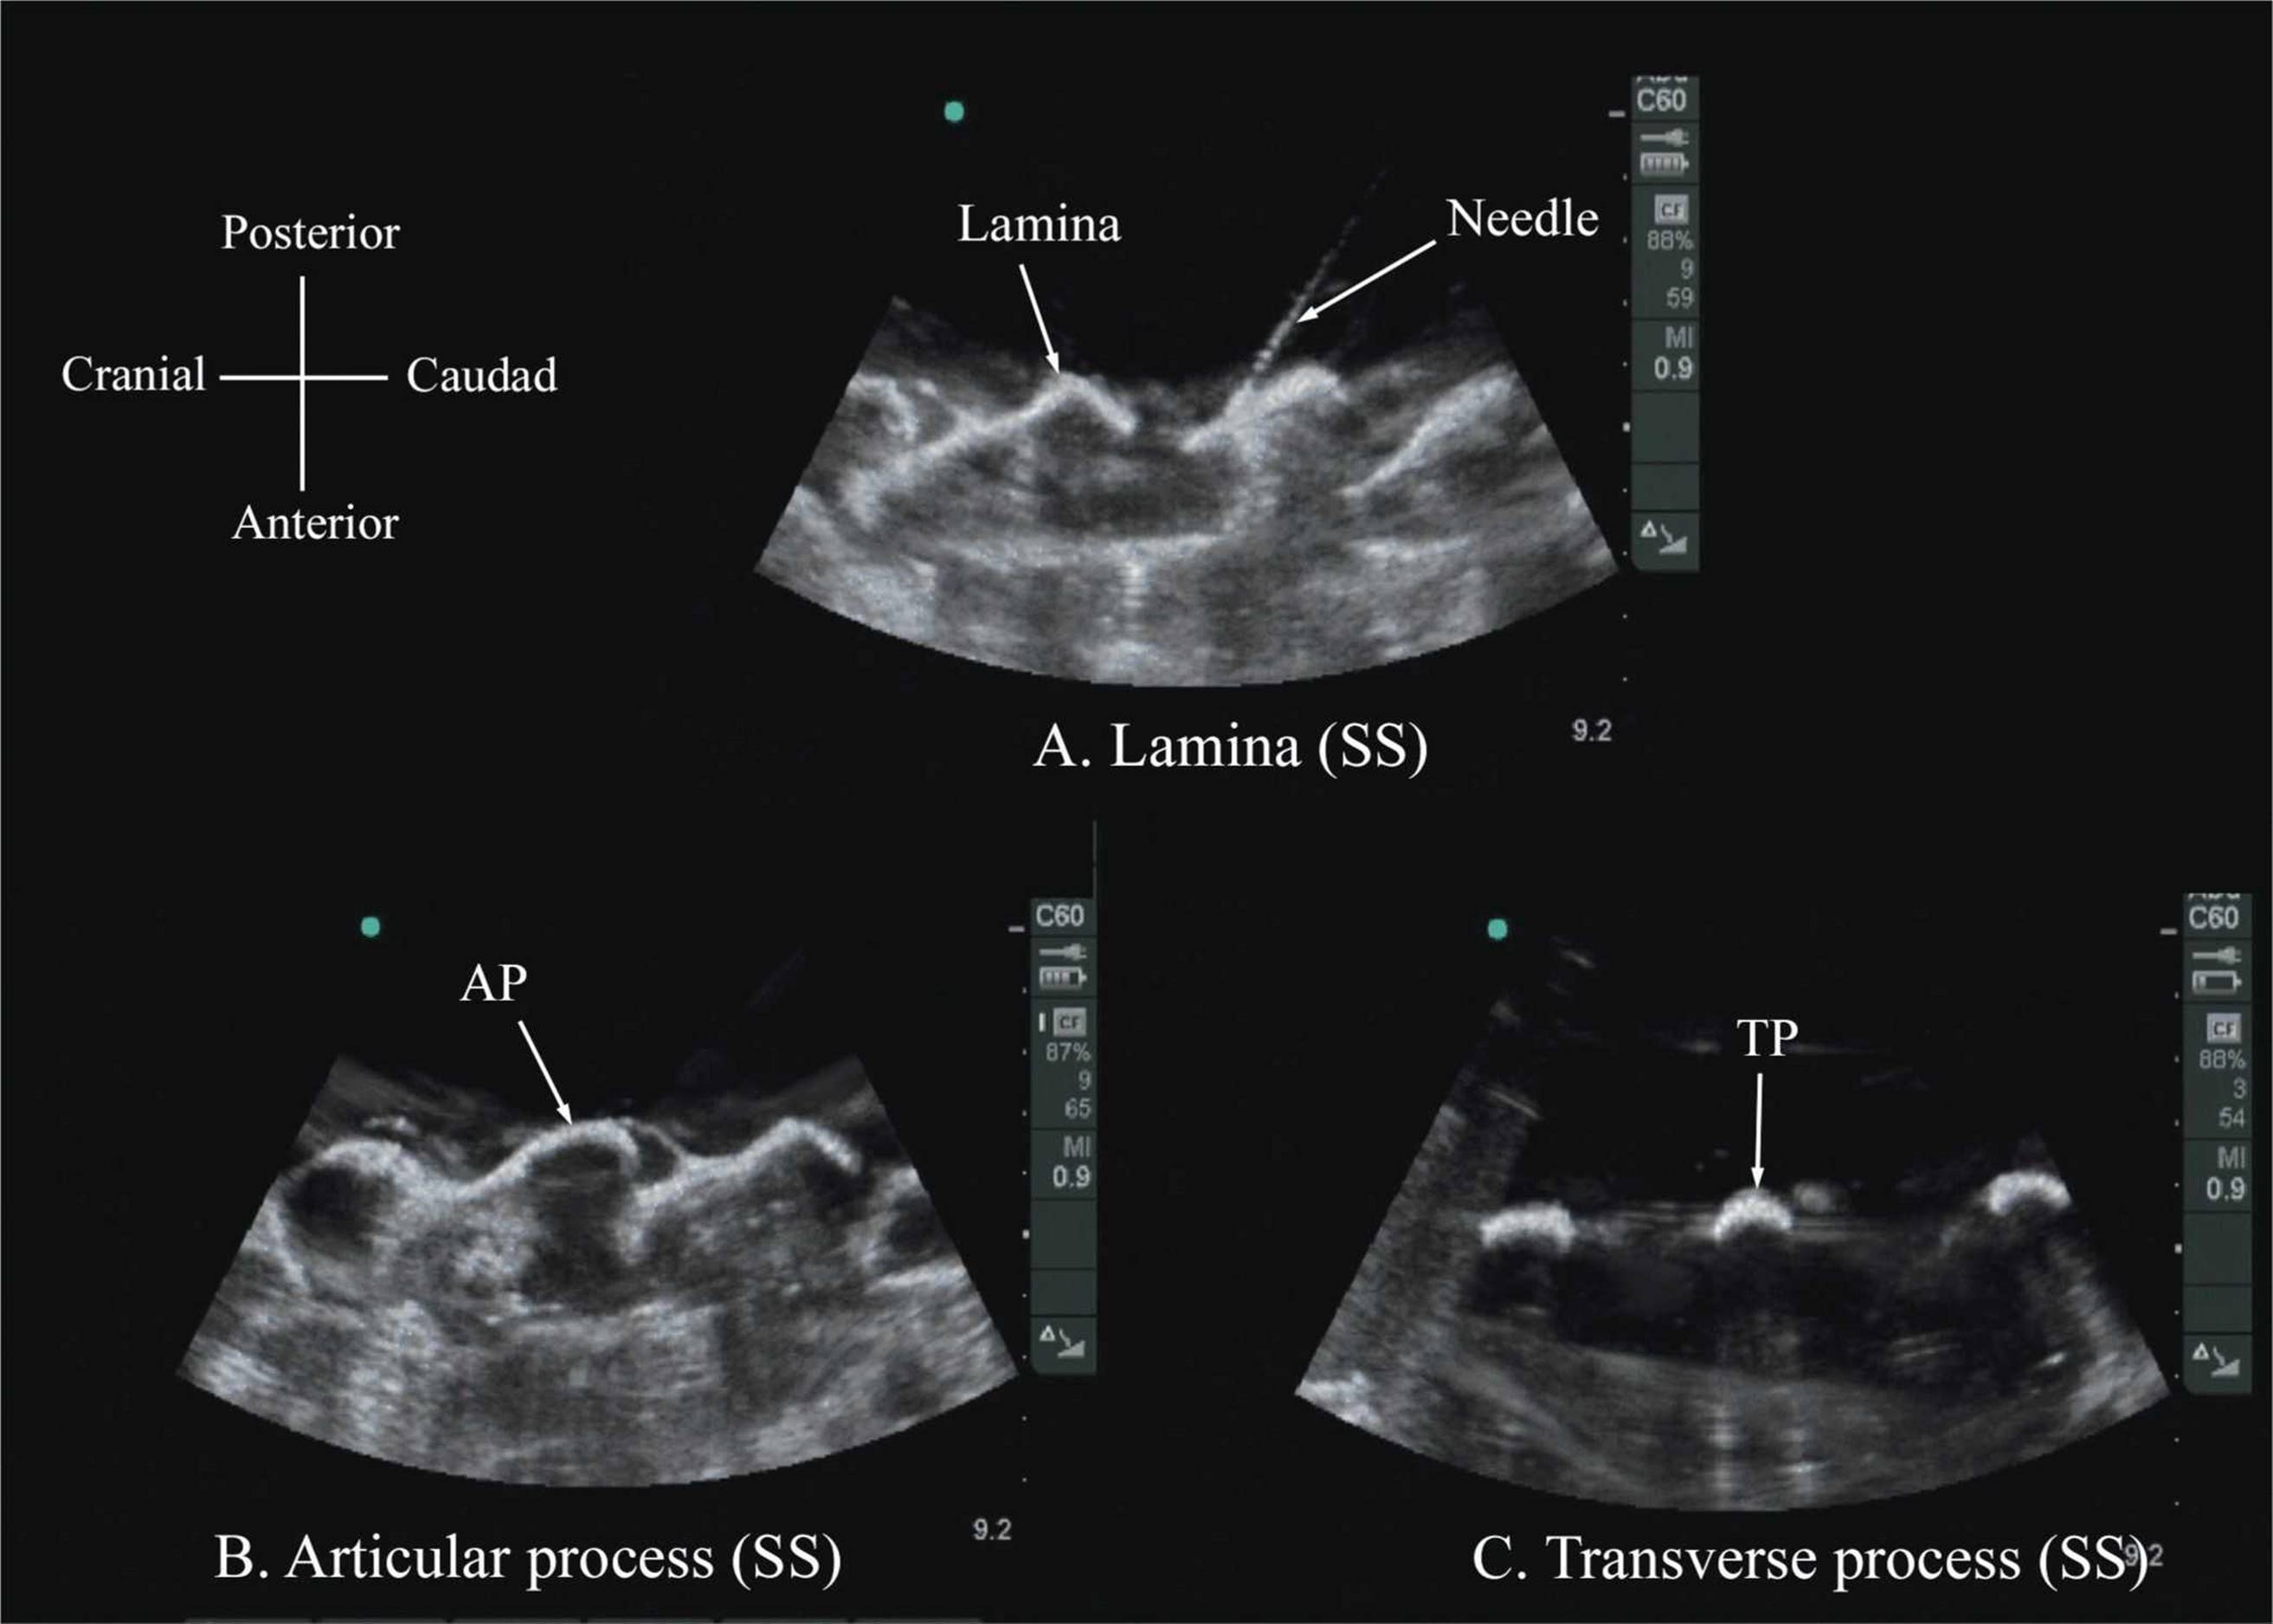

The water-based spine phantom18 is based on a model described previously by Greher and colleagues to study the osseous anatomy of relevance to US-guided lumbar facet nerve block.20 The model is prepared by immersing a commercially available lumbosacral spine model in a water bath. A low-frequency curved array transducer submerged into water is used to scan in the transverse and sagittal axes (Figure 44-3A). Each osseous element of the spine produces a “characteristic” sonographic pattern. The ability to recognize these sonographic patterns is an important step toward understanding the sonoanatomy of the spine. Representative US images of the spinous process, lamina, articular processes, and the transverse process from the water-based spine phantom are presented in Figures 44-3 and 44-6. The advantage of this water-based spine phantom is that water produces an anechoic (black) background against which the hyperechoic reflections from the bone are clearly visualized. The water-based spine phantom allows a see-through real-time visual validation of the sonographic appearance of a given osseous element by performing the scan with a marker (e.g., a needle) in contact with it (Figure 44-6A). The described model is also inexpensive, easily prepared, requires little time to set up, and can be used repeatedly without deteriorating or decomposing, as animal tissue-based phantoms do.

FIGURE 44-6. Paramedian sagittal sonogram of the (A) lamina, (B) articular process, and (C) transverse process from the water-based spine phantom. Note the needle in contact with the lamina in (A), a method that was used to validate the sonographic appearance of the osseous elements in the phantom.